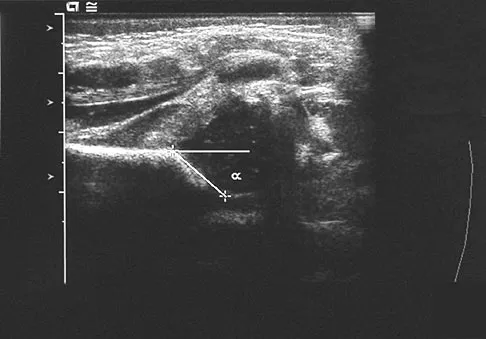

A newborn girl with an isolated unilateral dislocatable hip is placed in a Pavlik harness with the hips flexed 100 degrees and at resting abduction. Figure 23 shows an ultrasound obtained 2 weeks later. What is the next step in management?